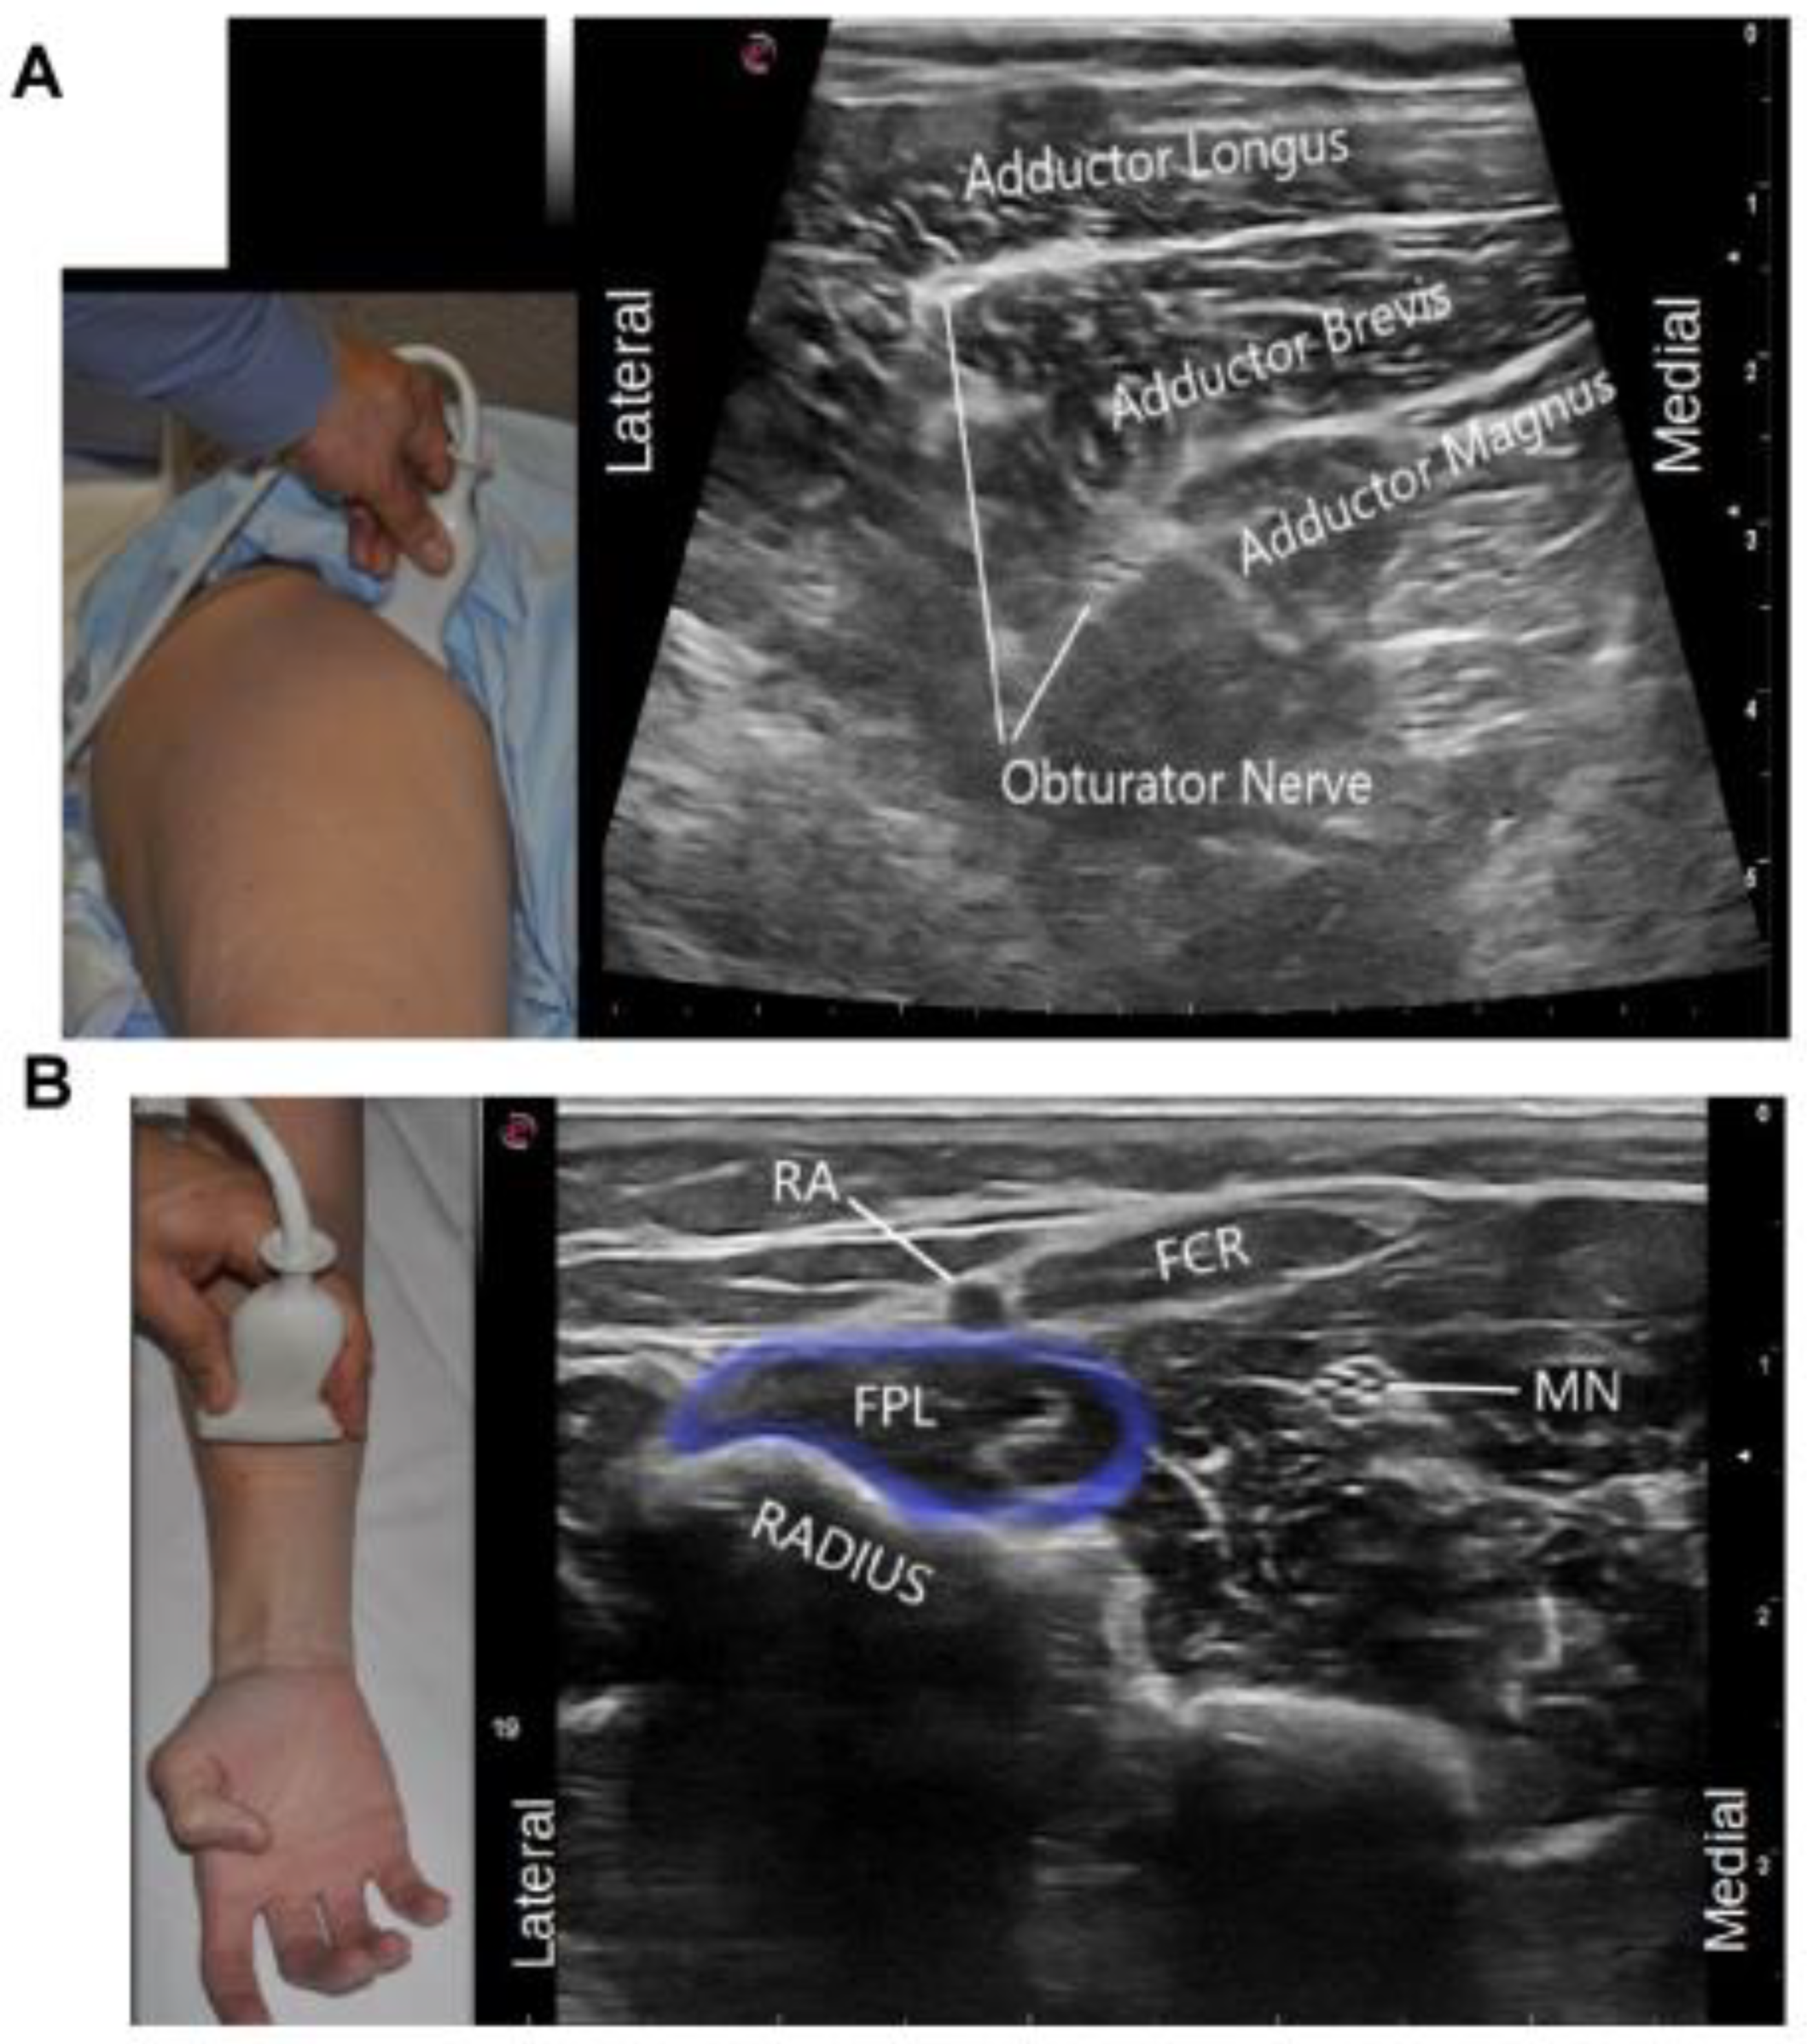

4.5. Visual Ergonomics Using Ultrasound